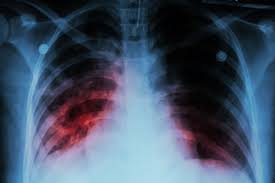

Early detection of lung cancer using imaging and diagnostic tools for prompt and effective treatment planning.